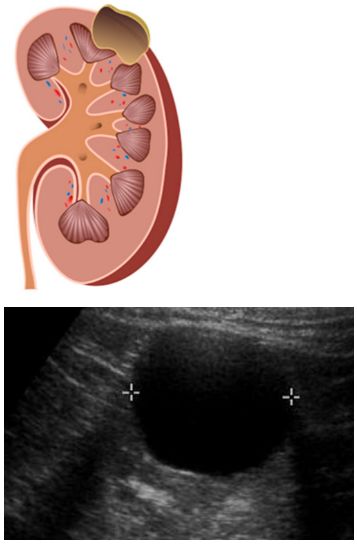

단순 물혹은 가장 흔한 형태의 콩팥 물혹입니다. 하나의 방으로 구성되어 있으며, 내부에 맑은 액체만을 포함하고 있습니다. 대부분의 경우 악성 변화의 가능성이 매우 낮아 정기적인 관찰만으로도 충분한 경우가 많습니다. 단순 물혹은 초음파 검사에서 내부가 비어 있고 경계가 명확하게 보입니다.

복합 물혹은 초음파 검사에서 내부에 불균일한 구조를 보이며, 여러 개의 방이 있거나 고형 성분이 포함된 것을 나타냅니다.